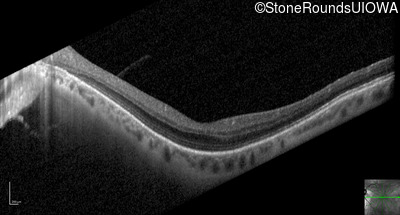

Optical Coherence Tomography - Left - 20/25 +2

Exemplar / OCT Stack